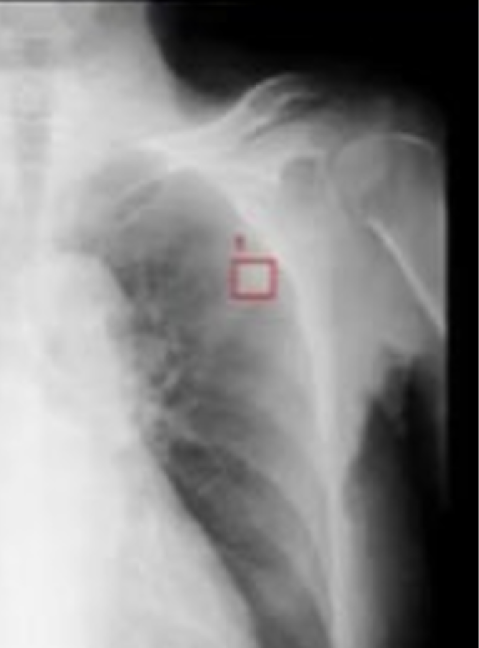

胸部CR×肺結節

EIRL Lung Nodule

胸部X線画像より、肺結節の形状に類似した領域を検出します

- クリニックで、ワンマン読影の補助として

- 検診で、膨大な読影の見落とし防止として

- 病院で、胸部が専門ではない診療科の先生の補助として

エルピクセル株式会社より提供を受けている医療機器「医用画像解析ソフトウェア EIRL X-ray Lung nodule」を搭載しております。